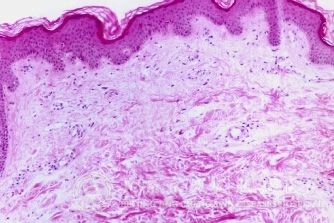

北京京城皮肤医院指出:只要与生殖器梅毒患者发生过性关系的人,在2至3周后,在生殖器或身体其他部位可出现单个或多个较硬的红色小肿块,不痛也不痒,表面常溃烂,医学上称硬下疳。

一期生殖器梅毒的硬下疳内有很多梅螺旋体,常伴有局部淋巴结肿大。传染性很强。